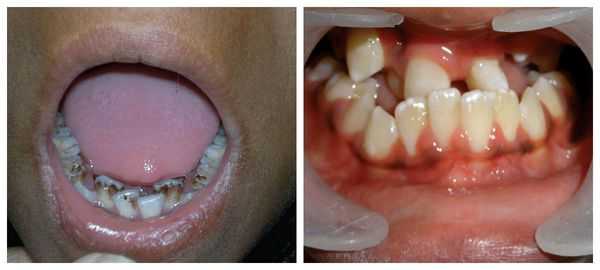

о Уши: микротия, преаурикулярные «метки» или ямки, атрезия слухового прохода о Лицо:

- Макростомия

- Асимметрия лица:

Отклонение подбородка в сторону поражения

Уменьшение размеров лица

- Челюсти и зубы:

Маленький мыщелок или его аплазия

Элевация окклюзионной плоскости

Импактные зубы на стороне поражения

- Аномалии развития зубов и задержка их развития